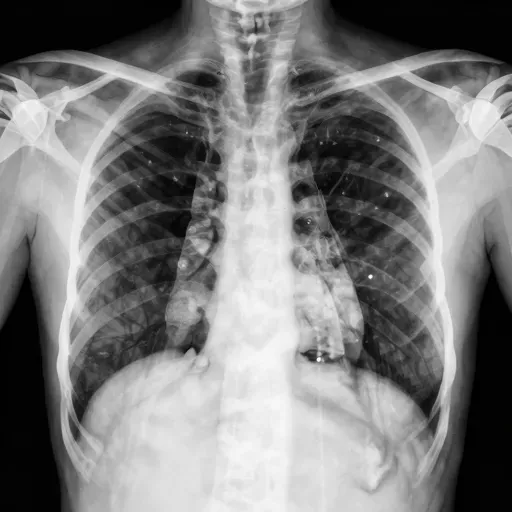

肺结核

Bệnh lao

Hình ảnh:

肺

Phổi